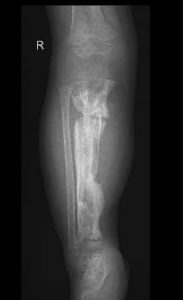

Dr. Feltes und Dr. Weber hatten für heute geplant die kleine Chantal (Name geändert) zu operieren. Geplant war den Tibiadefekt rechts mit einem Fibulatransfer zu decken. So gegen 13 Uhr wurden die beiden in den OP gerufen.

Das war die Ausgangssituation.

Und dies das Ergebnis nach 2-stündiger Operation.